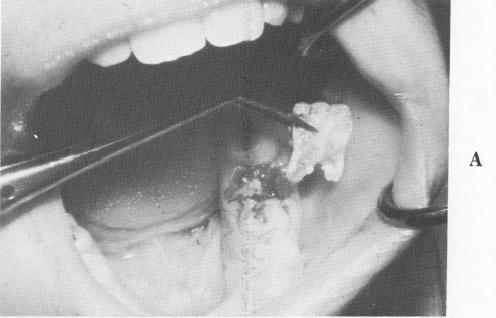

Fig. 8-70. A, The internal surface of the buccal half of a completely sagittally fractured mandibular first molar. B, Another view showing the buccal surface of the crown and roots. The lingual half of the tooth is still in the bone.